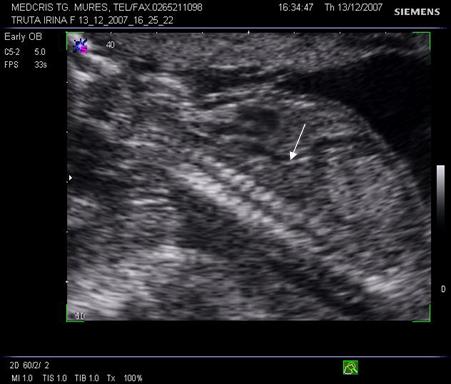

Doppler venos

Vena ombilicala - fluxul vascular poate fi apreciat in cordonul ombilical sau in abdomenul fetal. De obicei spectrul este monofazic daca fatul este in repaus motor si respirator.

Aspecte patologice ale spectrului Doppler constau in pulsatii venoase. Acestea par fiziologice, in timpul miscarilor respiratorii, iar patologice in trim. II si III in anomalii cardiace, aritmii sau insuficiente cardiace. Daca sunt asociate cu absenta fluxului end - diastolic in artera ombilicala, e vorba de insuficienta placentara si mortalitate de 50 - 60% [10,12].

Fig. nr. 327. Doppler cu pulsatii in vena ombilicala, in RCIU marcat la 34 sapt.

Ductul venos

In sectiune sagitala ductul venos apare ca o continuare a venei ombilicale spre vena cava inferioara. Inclinatia creste de la 7 la 48 la locul de unire cu vena cava. Aspectul este de "trompeta" de la circa 17 saptamani.[14,17]

Fig.nr. 328. Schema ductului venos( cu doua sageti, sageata unica indica directia fluxului sangvin,adaptat dupa Mihu[17] )

Aspectul eco Doppler normal in ductul venos este de sistola ventriculara, diastola ventriculara, contractie atriala, deci aspect trifazic.

Ductul venos creaza o comunicare intre sistemul venos periferic ombilical si sistemul venos central al fatului. Gradientul presional in ductul venos se modifica in caz de suferinta fetala.

Daca are loc centralizarea circulatiei, prin scaderea presiunii venoase centrale, scade presiunea in ductul venos in timpul contractiei atriale, cu aparitia reverse - flow.( unda a negativa ) [19]

Fig. nr.329. Ductus venosus( sageata ) la o sarcina de 16 sapt,. sectiunea sagitala fetala

Fig. nr. 330. Ductus venosus la doppler pulsat cu CFM , la o sarcina de 27 sapt. Se remarca aspectul normal trifazic al undei .

Fig. nr. 331. Ductus venosus la doppler pulsat si CFM , la 21 sapt, fat in sectiunea transversala a stomacului